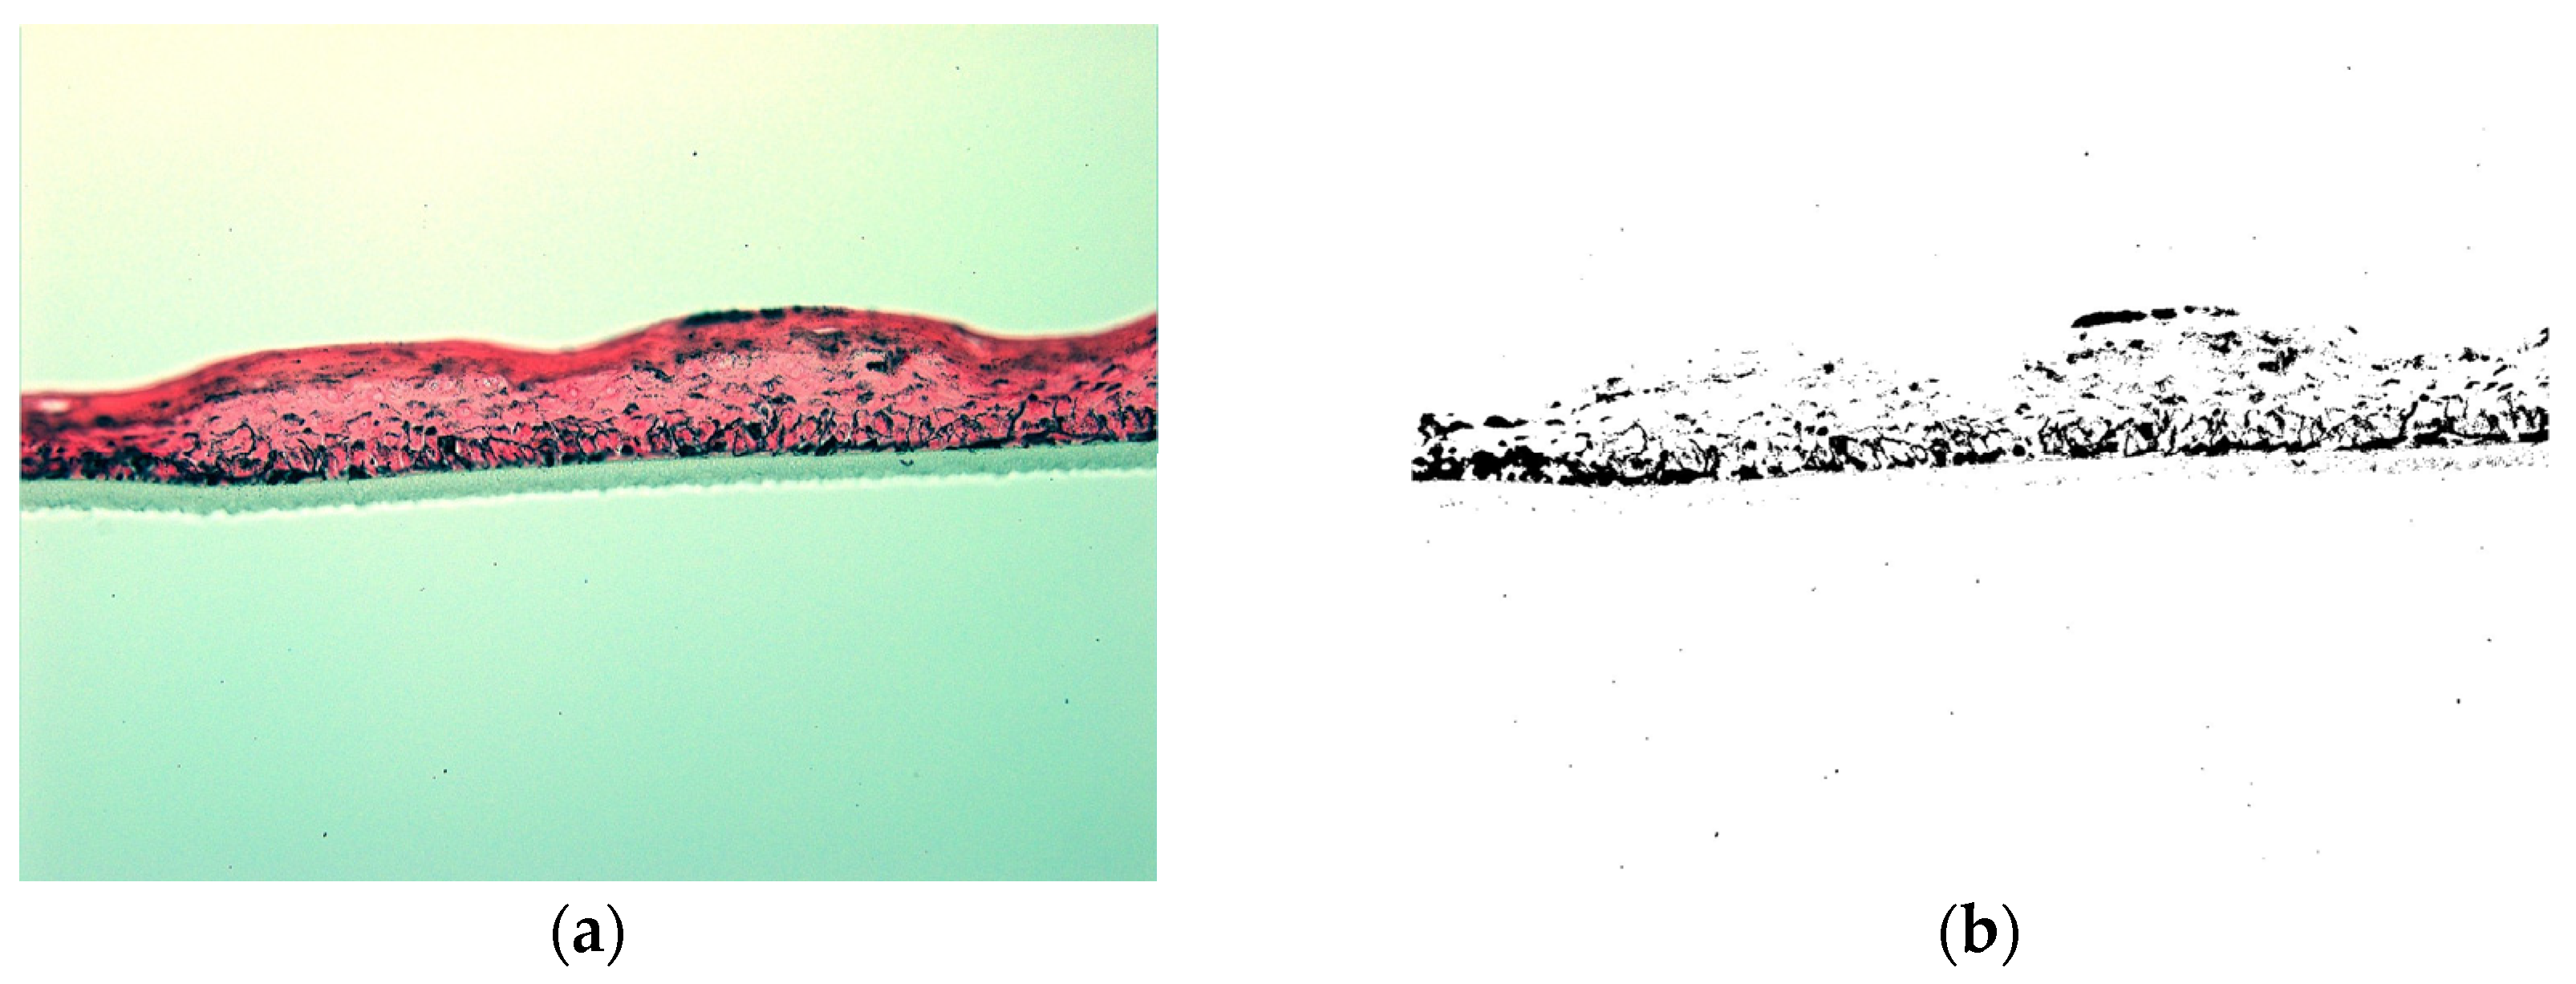

3.7. Depigmenting Effect of the Combination in a 3D Epidermis Model